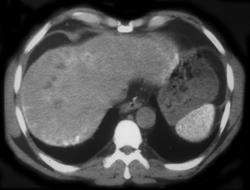

Sickle Cell Disease & Auto infarcted Spleen